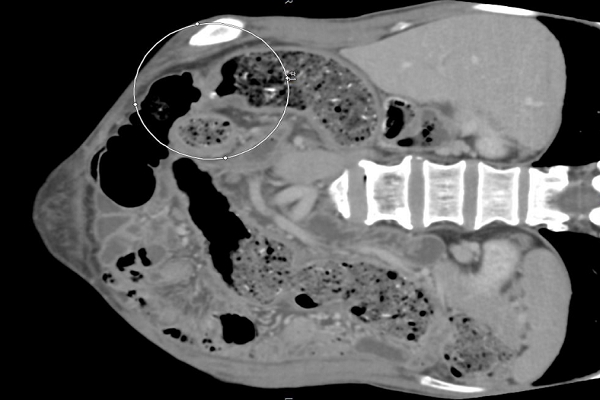

Ngày 23.4, bác sĩ Nguyễn Ngọc Thao - Trưởng khoa ngoại tiêu hóa, Bệnh viện Hoàn Mỹ Sài Gòn cho biết kết quả kiểm tra cận lâm sàng cho thấy, bệnh nhân X. đã bị ung thư đại tràng di căn hạch biến chứng tắc ruột dọa vỡ.

"Bệnh nhân sau khi làm các xét nghiệm đã cho tiến hành chụp CT bụng thì phát hiện khối u đại tràng trái rất to, di căn hạch và biến chứng gây tắc ruột, các quai ruột giãn rất to nguy cơ vỡ đe dọa tính mạng bệnh nhân. Sau hội chẩn khẩn, bệnh nhân được mổ cấp cứu trong đêm, loại bỏ được khối u đại tràng rất to và khối hạch di căn quanh u, nhằm lưu thông ruột. Bệnh nhân sau đó đã được phục hồi”, bác sĩ Thao chia sẻ.